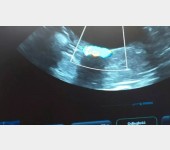

Gdyby nie Mikuś, nie prosiłabym Was o pomoc, ale on jest naszym słoneczkiem i chcemy mu pomóc. Post będzie długi, ale będę wdzięczna za przeczytanie. Mam na imię Karolina, mamy z chłopakiem trzy koty i psa. Ze względu na stan zdrowia pracuję w sklepie na pół etatu, mój chłopak w czasie koronawirusa został zwolniony, szuka pracy i pracuje dorywczo na czarno. Dotychczas jakoś sobie radziliśmy, było skromnie, ale byliśmy razem i mieliśmy cudowne zwierzaki. W styczniu nasz kocurek Mikuś zaczął chorować pojawił się krwiomocz, problemy z wypróżnianiem, pozycja bólowa, napięty brzuch. Pojechaliśmy do weterynarza i okazało się, że Mikuś ma w moczu mnóstwo kryształków struwitów i całkowicie zatkane jelita :( Został w klinice, poddano go narkozie, zrobiono lewatywę, badania moczu, dostał zastrzyki przeciwbólowe, rozkurczowe, antybiotyki, kapsułki na rozcieńczenie moczu i zalecenie karmienia dobrą mokrą karmą. Zapłaciliśmy 350 zł, później dodatkowo dokupiliśmy kapsułki za 65 zł, do tego karma urinary. To był dla nas ogromny strzał finansowy, bo dotychczas wystarczyło nam na opłatę mieszkania, rachunków i bardzo skromne jedzenie dla nas i zwierząt (a właściwie głównie dla nas, bo często woleliśmy kupić coś lepszego zwierzakom niż sobie). Niestety problemy Mikusia nawracały. Każda wizyta u lekarza to koszt 150-200 zł. Kolejne kapsułki, kolejna karma specjalistyczna i powoli zaczęliśmy się załamywać, czy damy radę temu sprostać finansowo.